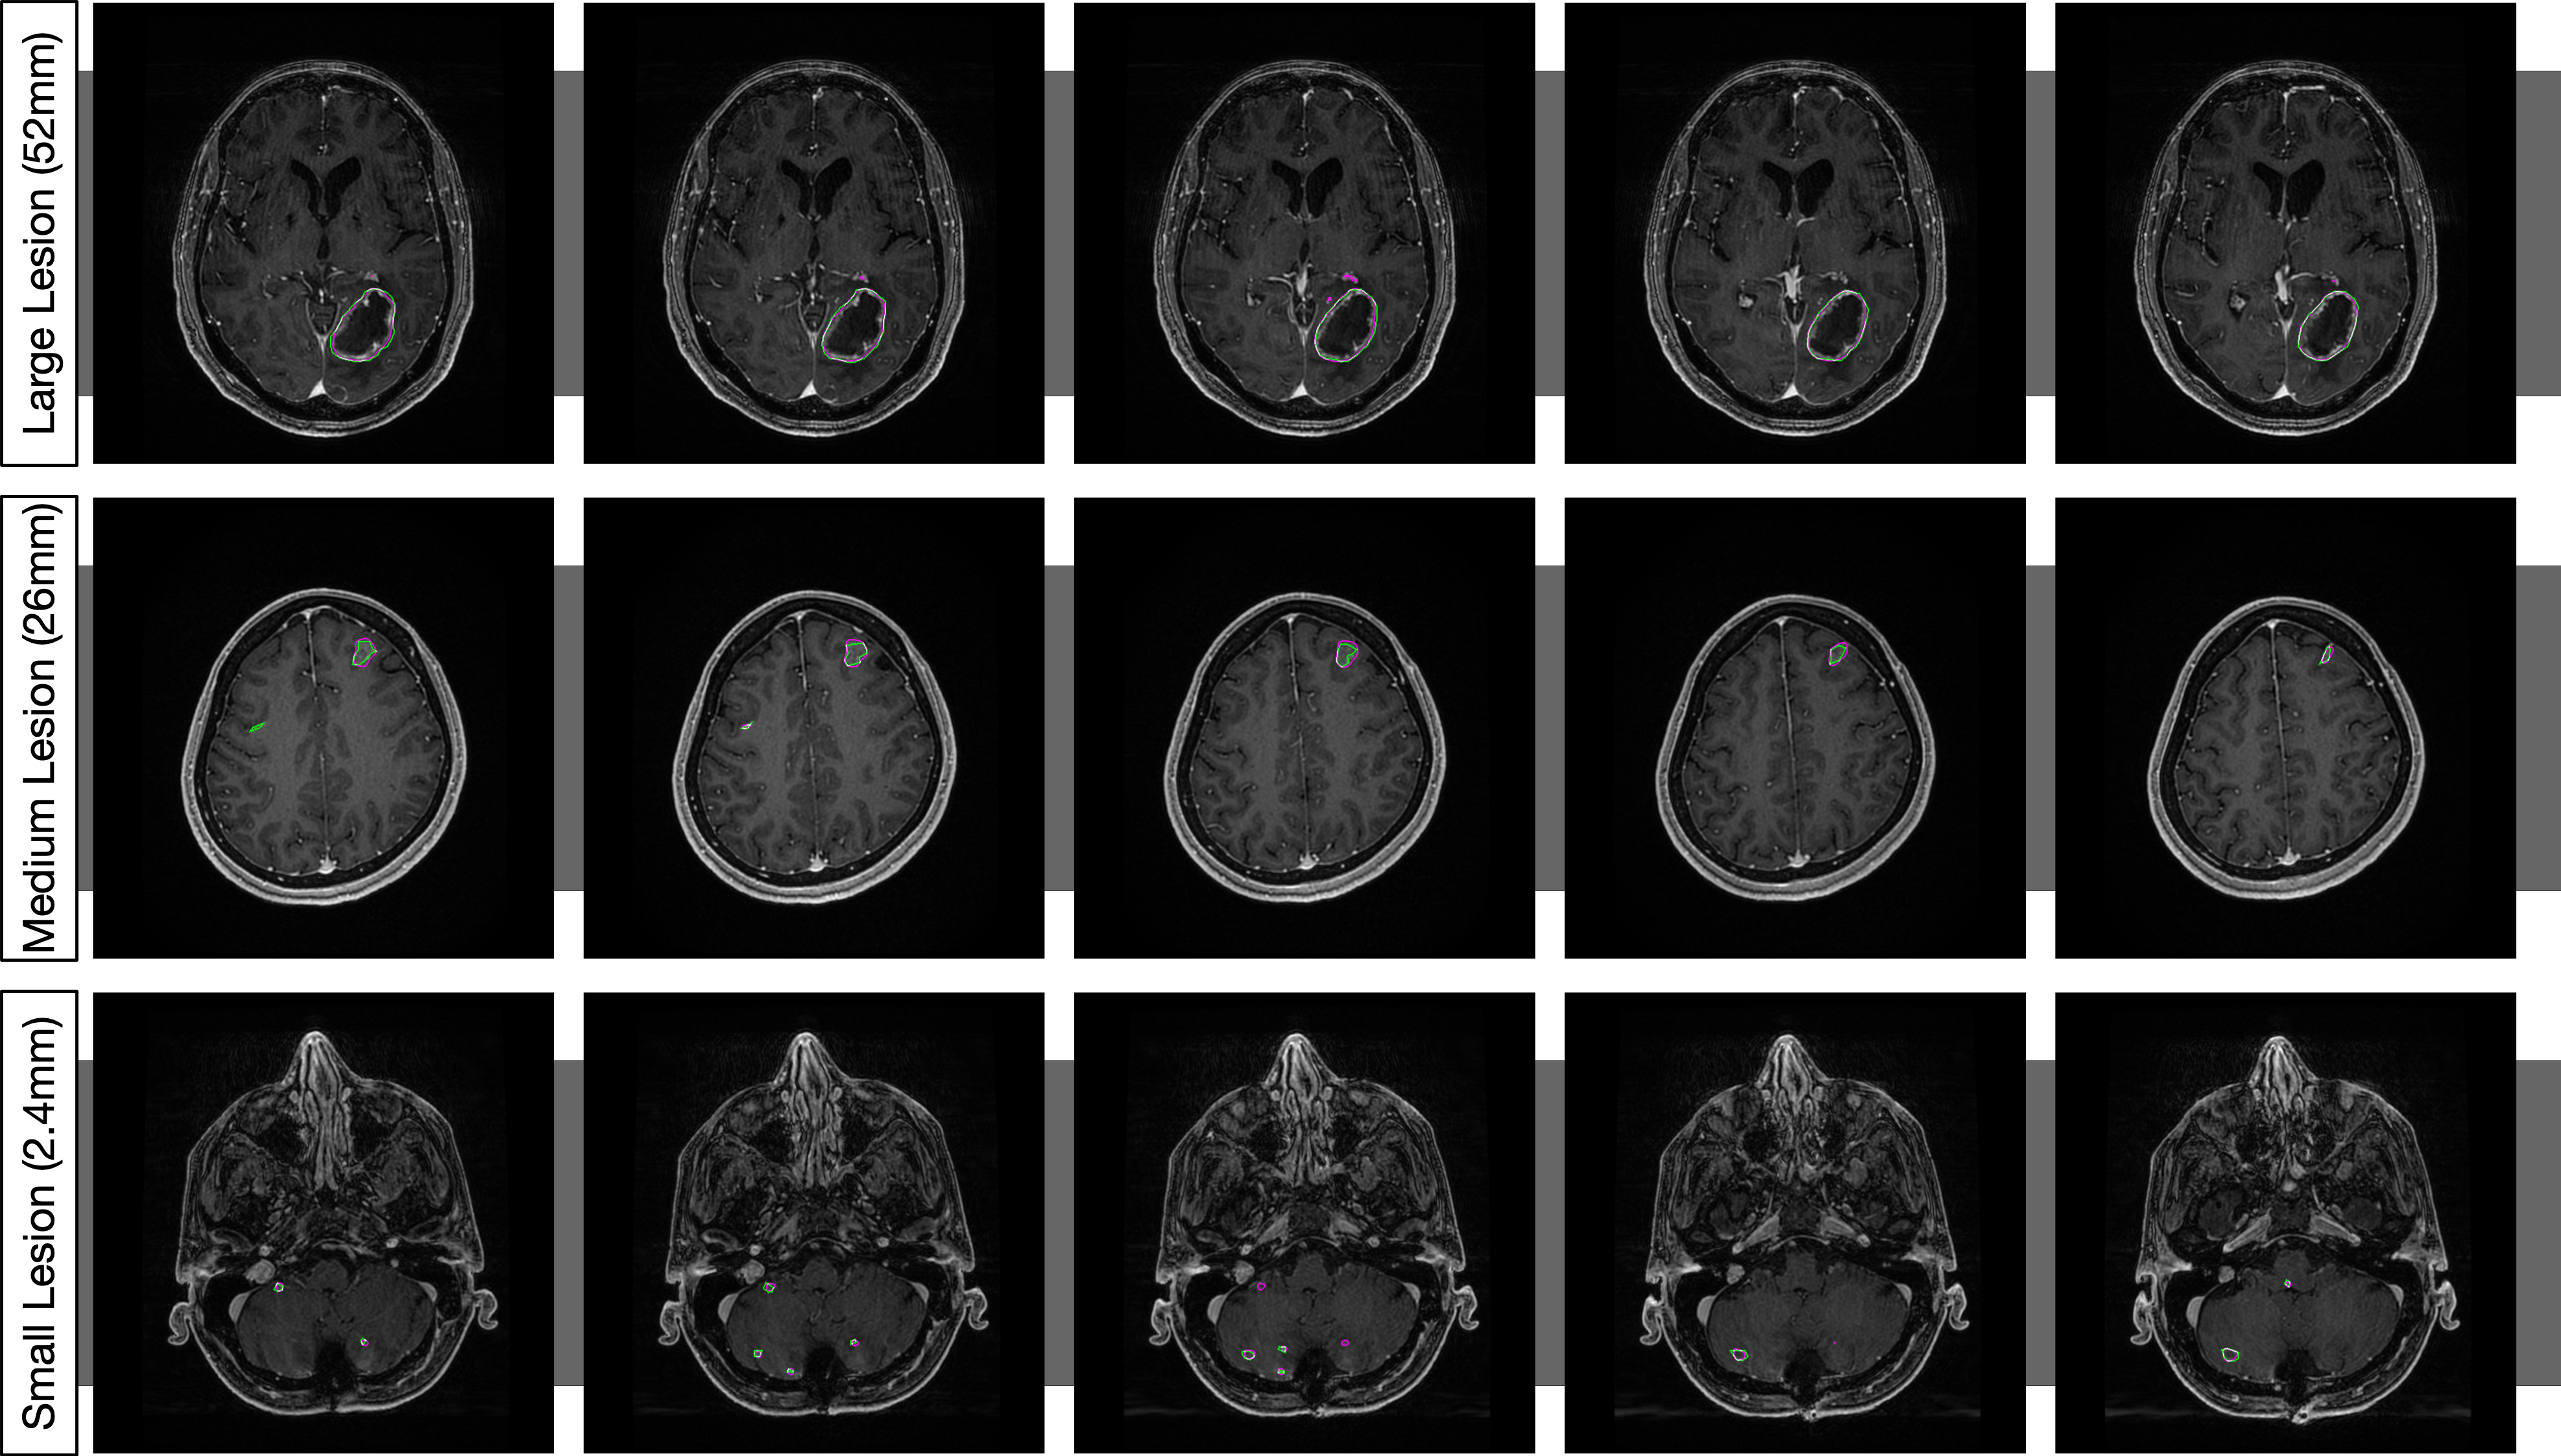

Figure LABEL:fig:qualitative shows representative images of the segmentations that result from training on the censored data. We can see the effects of different and hyperparameters on our segmentations in Figure 4. Increasing and decreasing both make the network more sensitive. However, decreasing better matches image-level gradients, which is advantageous for the task of segmentation. Figure 4 shows us the segmentation performance on different tiers of lesion sizes of the network. We can see that it performs well across a range of lesion sizes.

fig:qualitative

\subfigure[Hyperparameter Effects]

\subfigure[Segmentation Examples]